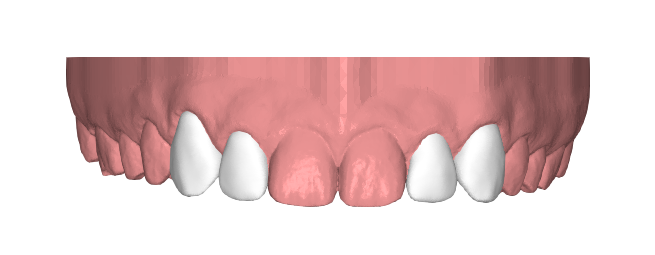

Desde Elevantia Solutions propusimos un Injectable Composite Design con carillas únicamente en esas piezas, para cerrar los espacios sin necesidad de limar sus dientes. Se trabajaron varias versiones del diseño hasta conseguir un resultado totalmente adaptado a sus expectativas, respetando al máximo la estructura dental natural al cerrar los espacios